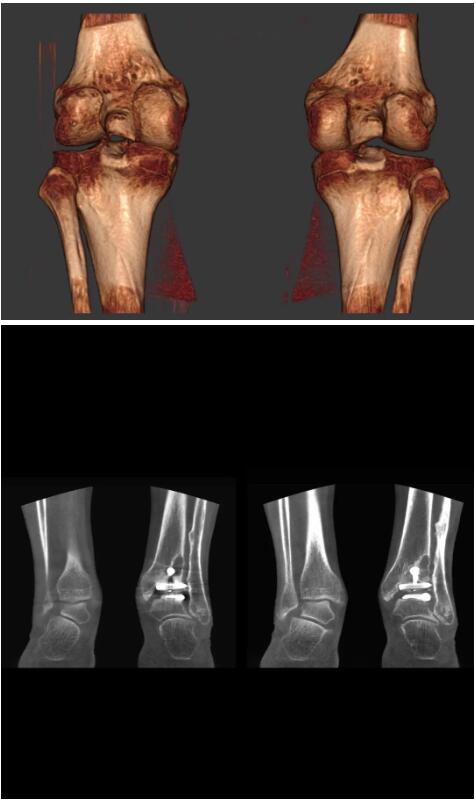

以下是這些“特立獨行”的CT所拍出來的圖像:

另外一款被稱為世界上最小的CT,它的重量僅300磅,不僅能夠掃查足部,還可以檢查膝蓋和上肢等。

以上介紹的CT均來自國外同一家公司,這些CT均配置了可視化軟件,可以進行切片、3D重建以及大型CT附帶的所有典型的操作功能。